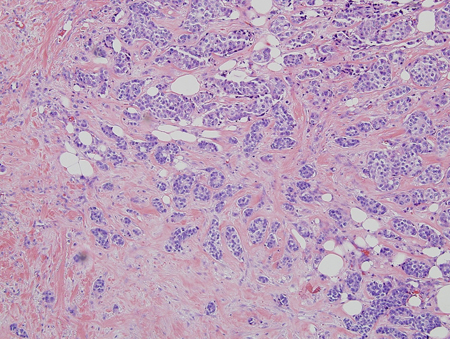

Biopsy is prompted by any irregular, rubbery, hard, fixed, or eccentric (not subareolar) mass; overlying nipple, areola, or skin abnormality; or axillary adenopathy. These findings are suggestive of breast cancer.[3][Figure caption and citation for the preceding image starts]: Histology: breast cancer; nests of malignant ductal carcinoma invading tissue; 10X magnificationFrom Minneapolis Veterans Affairs Medical Center pathology collection [Citation ends].

Histological findings of clusters of ducts (with epithelial hyperplasia if acute, and dilation alone when chronic), oedema, or inflammatory cells on a fibrous background indicate gynaecomastia.